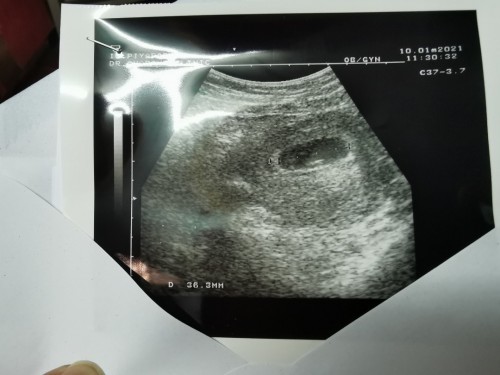

หมอบอกว่าท้องลม

ไปซาวด์มาอายุครรภ์7สัปดาห์ จะมีสิทธิ์เห็นทารกอีกมั้ยคะ😭😭